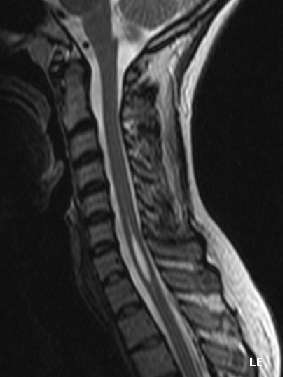

| An idiopathic syrinx. See the thin light grey shape inside the spinal cord, placed at centre in the bottom half of the above image. | |

Physicians now use magnetic resonance imaging (MRI) to diagnose syringomyelia. The MRI radiographer takes images of body anatomy, such as the brain and spinal cord, in vivid detail. This test will show the syrinx in the spine or any other conditions, such as the presence of a tumor. MRI is safe, painless, and informative and has greatly improved the diagnosis of syringomyelia.